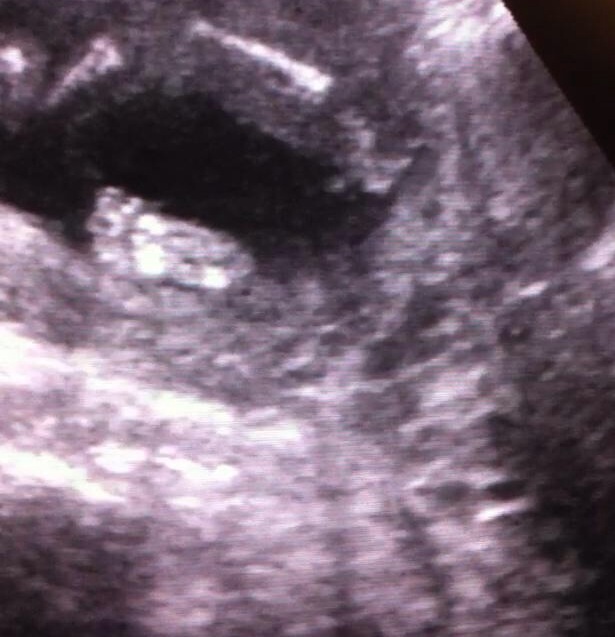

1st 2 pics were from 16 weeks scan everyone was unsure of those. ***NEW 3 pictures from 17 weeks scan

looks boyish on all of them.

Boy